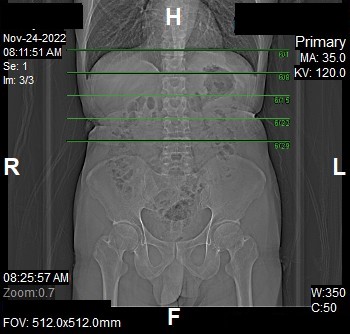

Nephrographic Phase

- Plan the Scan FOV (SFOV) box at topogram image.

- Set the top line at the upper abdomen.

- Set the bottom line at inferior ischial rami.

- Ensure the lateral line to cover patient’s body outline.

- Remind the patient before scanning as the breathing instruction will be given.

- Delay after cortico phase: 35 seconds (enhancement of renal parenchyma including medulla).

Reconstruction of Nephrographic Phase